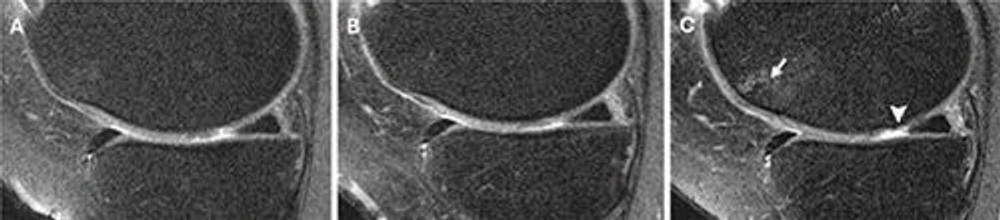

Figure 3. Knee MRI scans in a 57-year-old male participant in the Osteoarthritis Initiative who was administered a hyaluronic acid (HA) injection. Coronal intermediate-weighted knee MRI scans obtained (A) 2 years before injection, (B) at the time of injection, and (C) 2 years after injection show a well-preserved medial femoral cartilage, indicating a stable medial femoral cartilage through the pre- and postinjection time points. The medial femoral cartilage appears well-preserved across all three time points, suggesting no structural deterioration following the HA injection. These findings indicate stable cartilage morphologic structure during the 4-year observation period.